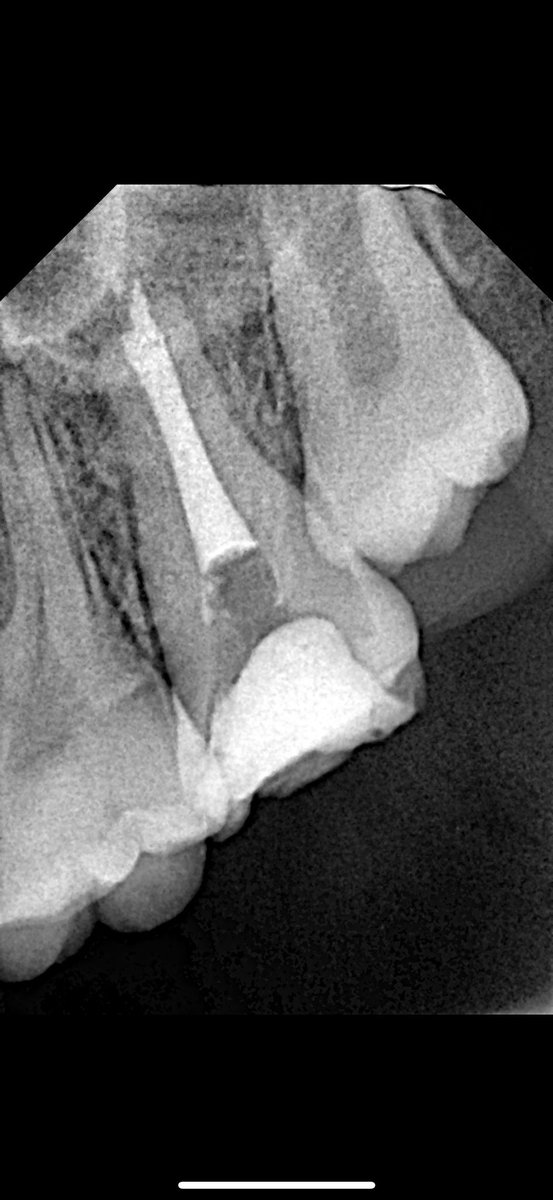

@Dr_abubakr1 @Mohammed1soo @HrbiHaneen @mutaz_alj @Khalid_6dent @amallllll775 الله يسلمك دكتورنا 🙏 ، تعتمد على الحاله بس هنا استخدمت راوند بير وحبيت تكون minimal عشان عليها كران